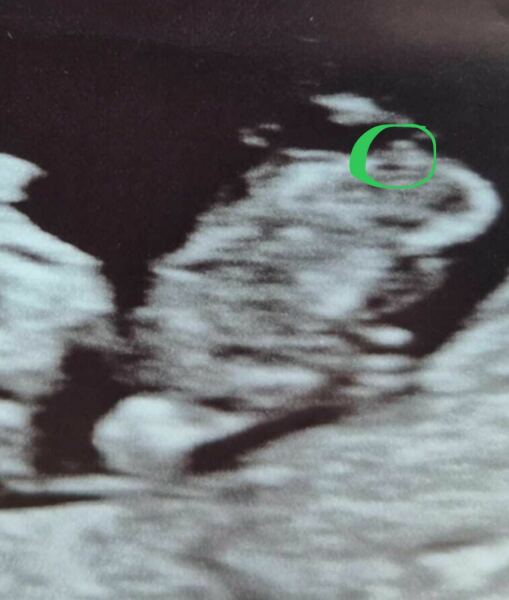

MilsCookie · 03/04/2025 23:17

I’m no expert at all and I may be wrong but the bit I’ve circled looks like the nub to me and it’s positioned like a boy nub… hard to explain! But I’ve done a lot of looking at girl v boy nub because I’m also pregnant haha! X

Nub theory guesses